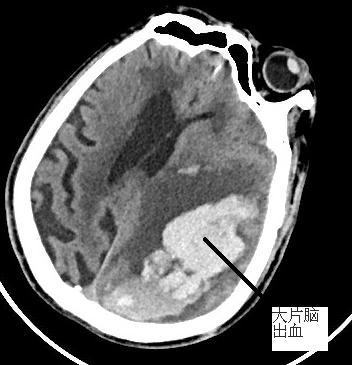

? ? ? 患者李大爺,83歲,走路的時(shí)候突然不能言語、四肢乏力,隨即出現(xiàn)昏迷,家人緊急送往我院急診科就醫(yī)。經(jīng)頭顱CT檢查,提示左側(cè)額頂葉、左側(cè)卵中、圓中心大面積腦出血,腦疝形成,腦出血量大,顱內(nèi)壓力高,需緊急清除腦內(nèi)血腫??紤]到患者年齡高、體質(zhì)差、手術(shù)風(fēng)險(xiǎn)高,我院神經(jīng)外科立即與福醫(yī)大附二院神經(jīng)外科當(dāng)班專家研討病情,根據(jù)患者實(shí)際情況,討論決定使用微創(chuàng)治療,擬給予神經(jīng)內(nèi)鏡下行腦內(nèi)血腫清除。在征得家屬知情同意后,立即進(jìn)行手術(shù),手術(shù)順利。術(shù)后,復(fù)查頭顱CT,發(fā)現(xiàn)腦內(nèi)血腫大部分已清除,顱內(nèi)壓明顯下降,偏移的腦中線較之前有恢復(fù),患者意識障礙得到較大改善,病情相對穩(wěn)定,后續(xù)繼續(xù)觀察治療。

治前VS治療后? ? ? ? ? ?